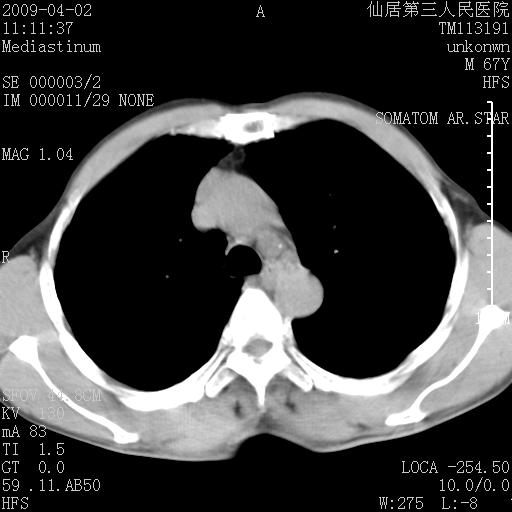

患者老年男性,乏力畏寒来诊,摄胸片示右下肺感染性病变,抗炎两周后复查胸片,无好转有进展。

后做ct平扫表现如下: